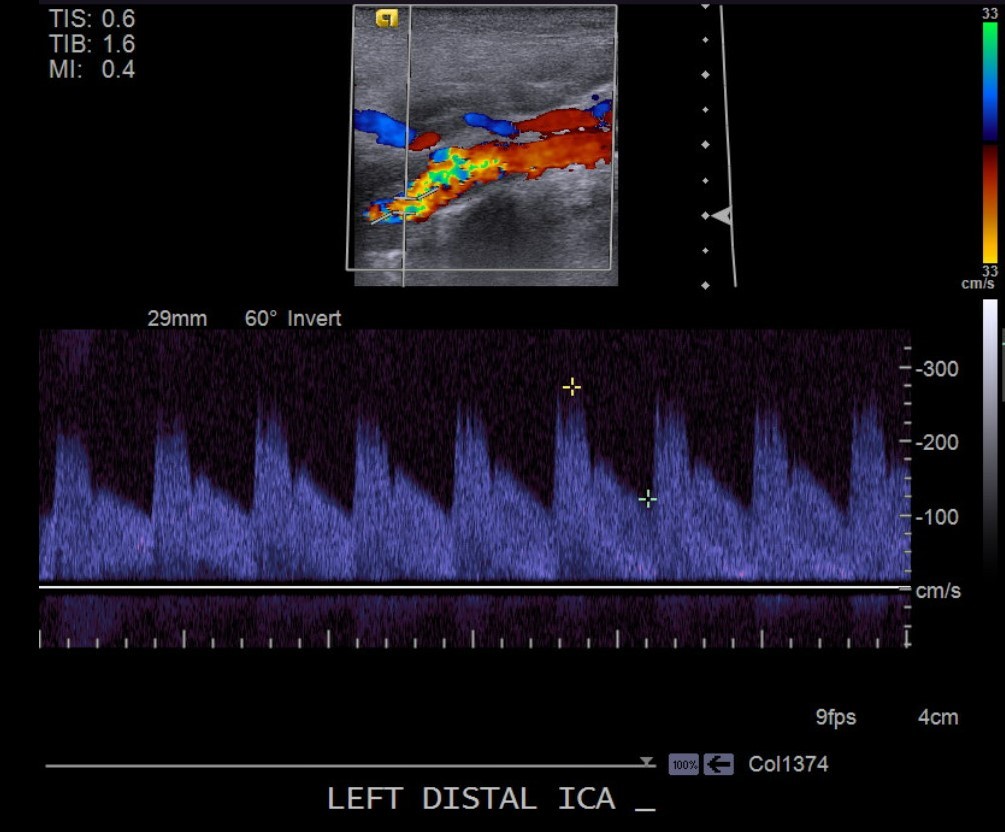

Some vascular abnormalities can cause a pulsatile tinnitus. Some patients describe this pulsation as whooshing. We don’t know the mechanism for a whooshing sound in ear sensation. The carotid arteries could be the cause in FMD. At least, that is the theory. In FMD, the carotid arteries are often tortuous. Also, there is often abnormal flow. Distal flow velocity is often elevated. These may result in abnormal sounds in the ears.